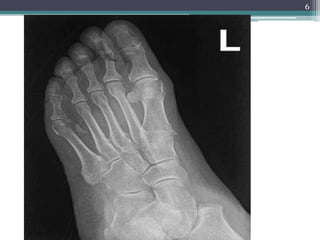

EXAMPLES

1. APLASIA: congenital absence of digit or rib

2. FORMATION OF EXTRA BONE:

supernumerary digit or ribs

3. ABNORMAL FUSION OF BONE:

premature closure

5

6